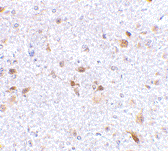

Below: Immunohistochemistry of PDL-2 in mouse brain tissue with PDL-2 antibody at 2.5 µg/ml.